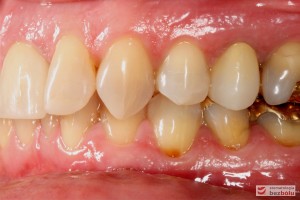

Do naszej placówki zgłosiła się starannie planująca swoje działania Europejka, mieszkająca na stałe w Kotlinie Jeleniogórskiej. Jej oczekiwania dotyczyły bardzo metodycznie zaplanowanego planu leczenia. Celem jaki postawiła przed naszym zespołem lekarzy było wyeliminowanie wszystkich wątpliwych i nierokujących wypełnień, a także poprawa estetyki w zakresie lewego siekacza centralnego w szczęce. Został rozpisany blisko dwuletni plan wymiany zużytych i nieszczelnych wypełnień amalgamatowych i kompozytowych. Zaplanowano również przygotowanie endodontyczne wybranych zębów w szczęce i żuchwie, a także zaopatrzenie w inlay’e porcelanowe i korony ceramiczne wykonane w systemie e-max.